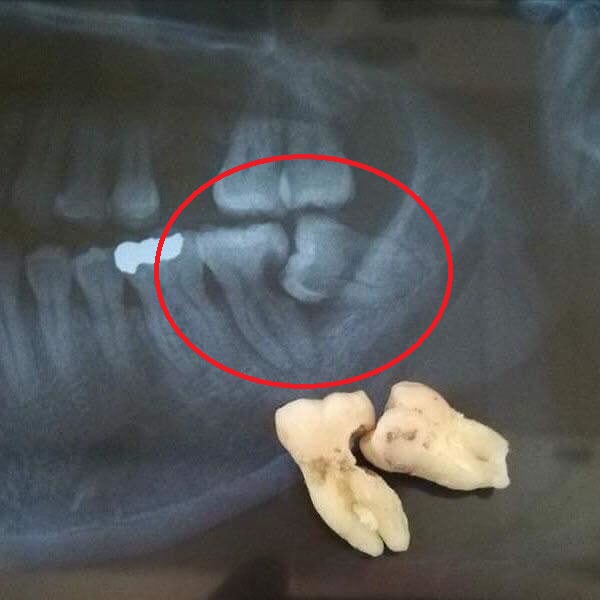

Normal halda insanın diş sırasında hər çənədə iki ədəd olmaqla, ümumilikdə dörd agıl dişi mövcuddur. Ağıl dişinin çıxması bəzi şəxslərdə heç bir kliniki əlamət və ya şikayətə səbəb olmasa da, bir çox hallarda müəyyən kliniki əlamətlərlə öyünü biruzə verir. Bu əlamətlər əsasən çənənin arxa tərəfində təzyiq, çənəni açıb baglama əsnasında agrı və məhdudlaşma kimi özünü göstərə bilir. Bu hallarda mütəxəssis konsultasiyasının önəmi olduqca böyükdür. Belə ki müayinə zamanı cərrah-stomatoloq kliniki və radioloji dəyərləndirmə apararaq dişin dogru pozisiyada yerləşib yerləşmədiyi, dişləmə çıxma ehtimalını, agıl dişinin çənəyə görə ölçüsü və çənə darlıgı kimi durumları dəyərləndirərək tətbiq edilməli olan müalicə taktikasını müəyyən edir.

Ağıl dişinin cərrahi çəkiminə göstərişlər isə aşağıdakılardır:

- Retensiyon ağıl dişinin spontan və ya ortodontik olaraq dişləmə çıxma ehtimalı mövcud deyilsə

- Ağıl dişi qonşu dişdə karies, sorulma, parodontal problemlər və s. yaradırsa